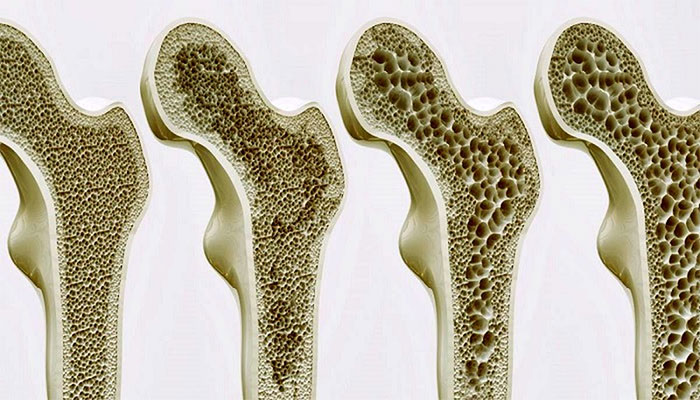

برای آنکه متوجه شویم پوکی استخوان چگونه اتفاق میافتد، باید فیزیولوژی استخوان را به صورت خلاصه بررسی میکنیم. استخوان یک بافت زنده و دائما در حال تغییر است که از یک لایه داخلی و یک لایه خارجی تشکیل میشود. لایه خارجی نازک و متراکم است و لایه داخلی دارای ساختار خانه-خانه و مشابه کندوی زنبور عسل است. بافت استخوان از فیبرهای پروتئینی مستحکم و با خاصیت الاستیکی به نام کلاژن، فسفات کلسیم و مواد معدنی دیگر تشکیل میشود. ترکیب شبکه کلاژن و فسفات کلسیم باعث استحکام و در عین حال انعطافپذیری در برابر ضربات میشود.

زمانی که حفرههای میان شبکهها در لایه داخلی، به علت تحلیل کلسیم بزرگ میشوند، استخوان به تدریج خالی شده و پوکی استخوان اتفاق میافتد. بنابراین استخوان شما ضعیف شده و با کوچکترین ضربهای دچار شکستگی میشود. از دست رفتن تراکم استخوانها به طور خاموش و بی سروصدا اتفاق میافتد و اغلب مواقع نیز هیچ علامتی تا زمان شکستگی ندارد.